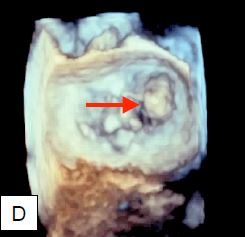

La bascule d'un feuillet dans l'OG, la non-coaptation laissant un large orifice en systole et la rupture de cordages ou de muscle papillaire sont pathognomoniques d'une IM sévère. La reconstruction 3D avec, entre autre, la vue de la mitrale "en-face" depuis l'OG comme l'aperçoit le chirurgien permet d'affiner le diagnostic et de mesurer les structures avec davantage précision; en général, les vues 2D tendent à sous-estimer l'étendue du prolapsus en comparaison des mesures 3D, car le plan de coupe est relativement arbitraire par rapport aux dimensions maximales des lésions (Figure 11.74) [20].

Figure 11.74 : Imagerie tri-dimensionnelle de l’IM vue depuis l’OG. A : fente (cleft) dans le feuillet antérieur; cette pathologie peut être très difficile à mettre en évidence en 2D alors qu'elle est bien visible en 3D. B : Image d’un prolapsus mitral de P1 ; on voit un cordage rupturé à l’extrémité du prolapsus (flèche). C : Prolapsus du feuillet antérieur (flèche) observé en protosystole. D : prolapsus de la commissure postérieure.